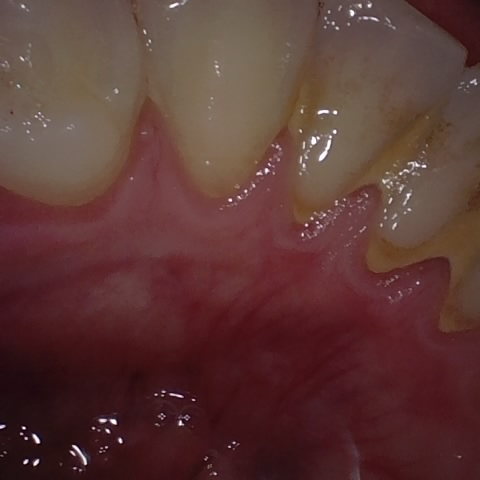

Annotated as "Good"

Original Image Rendering Image